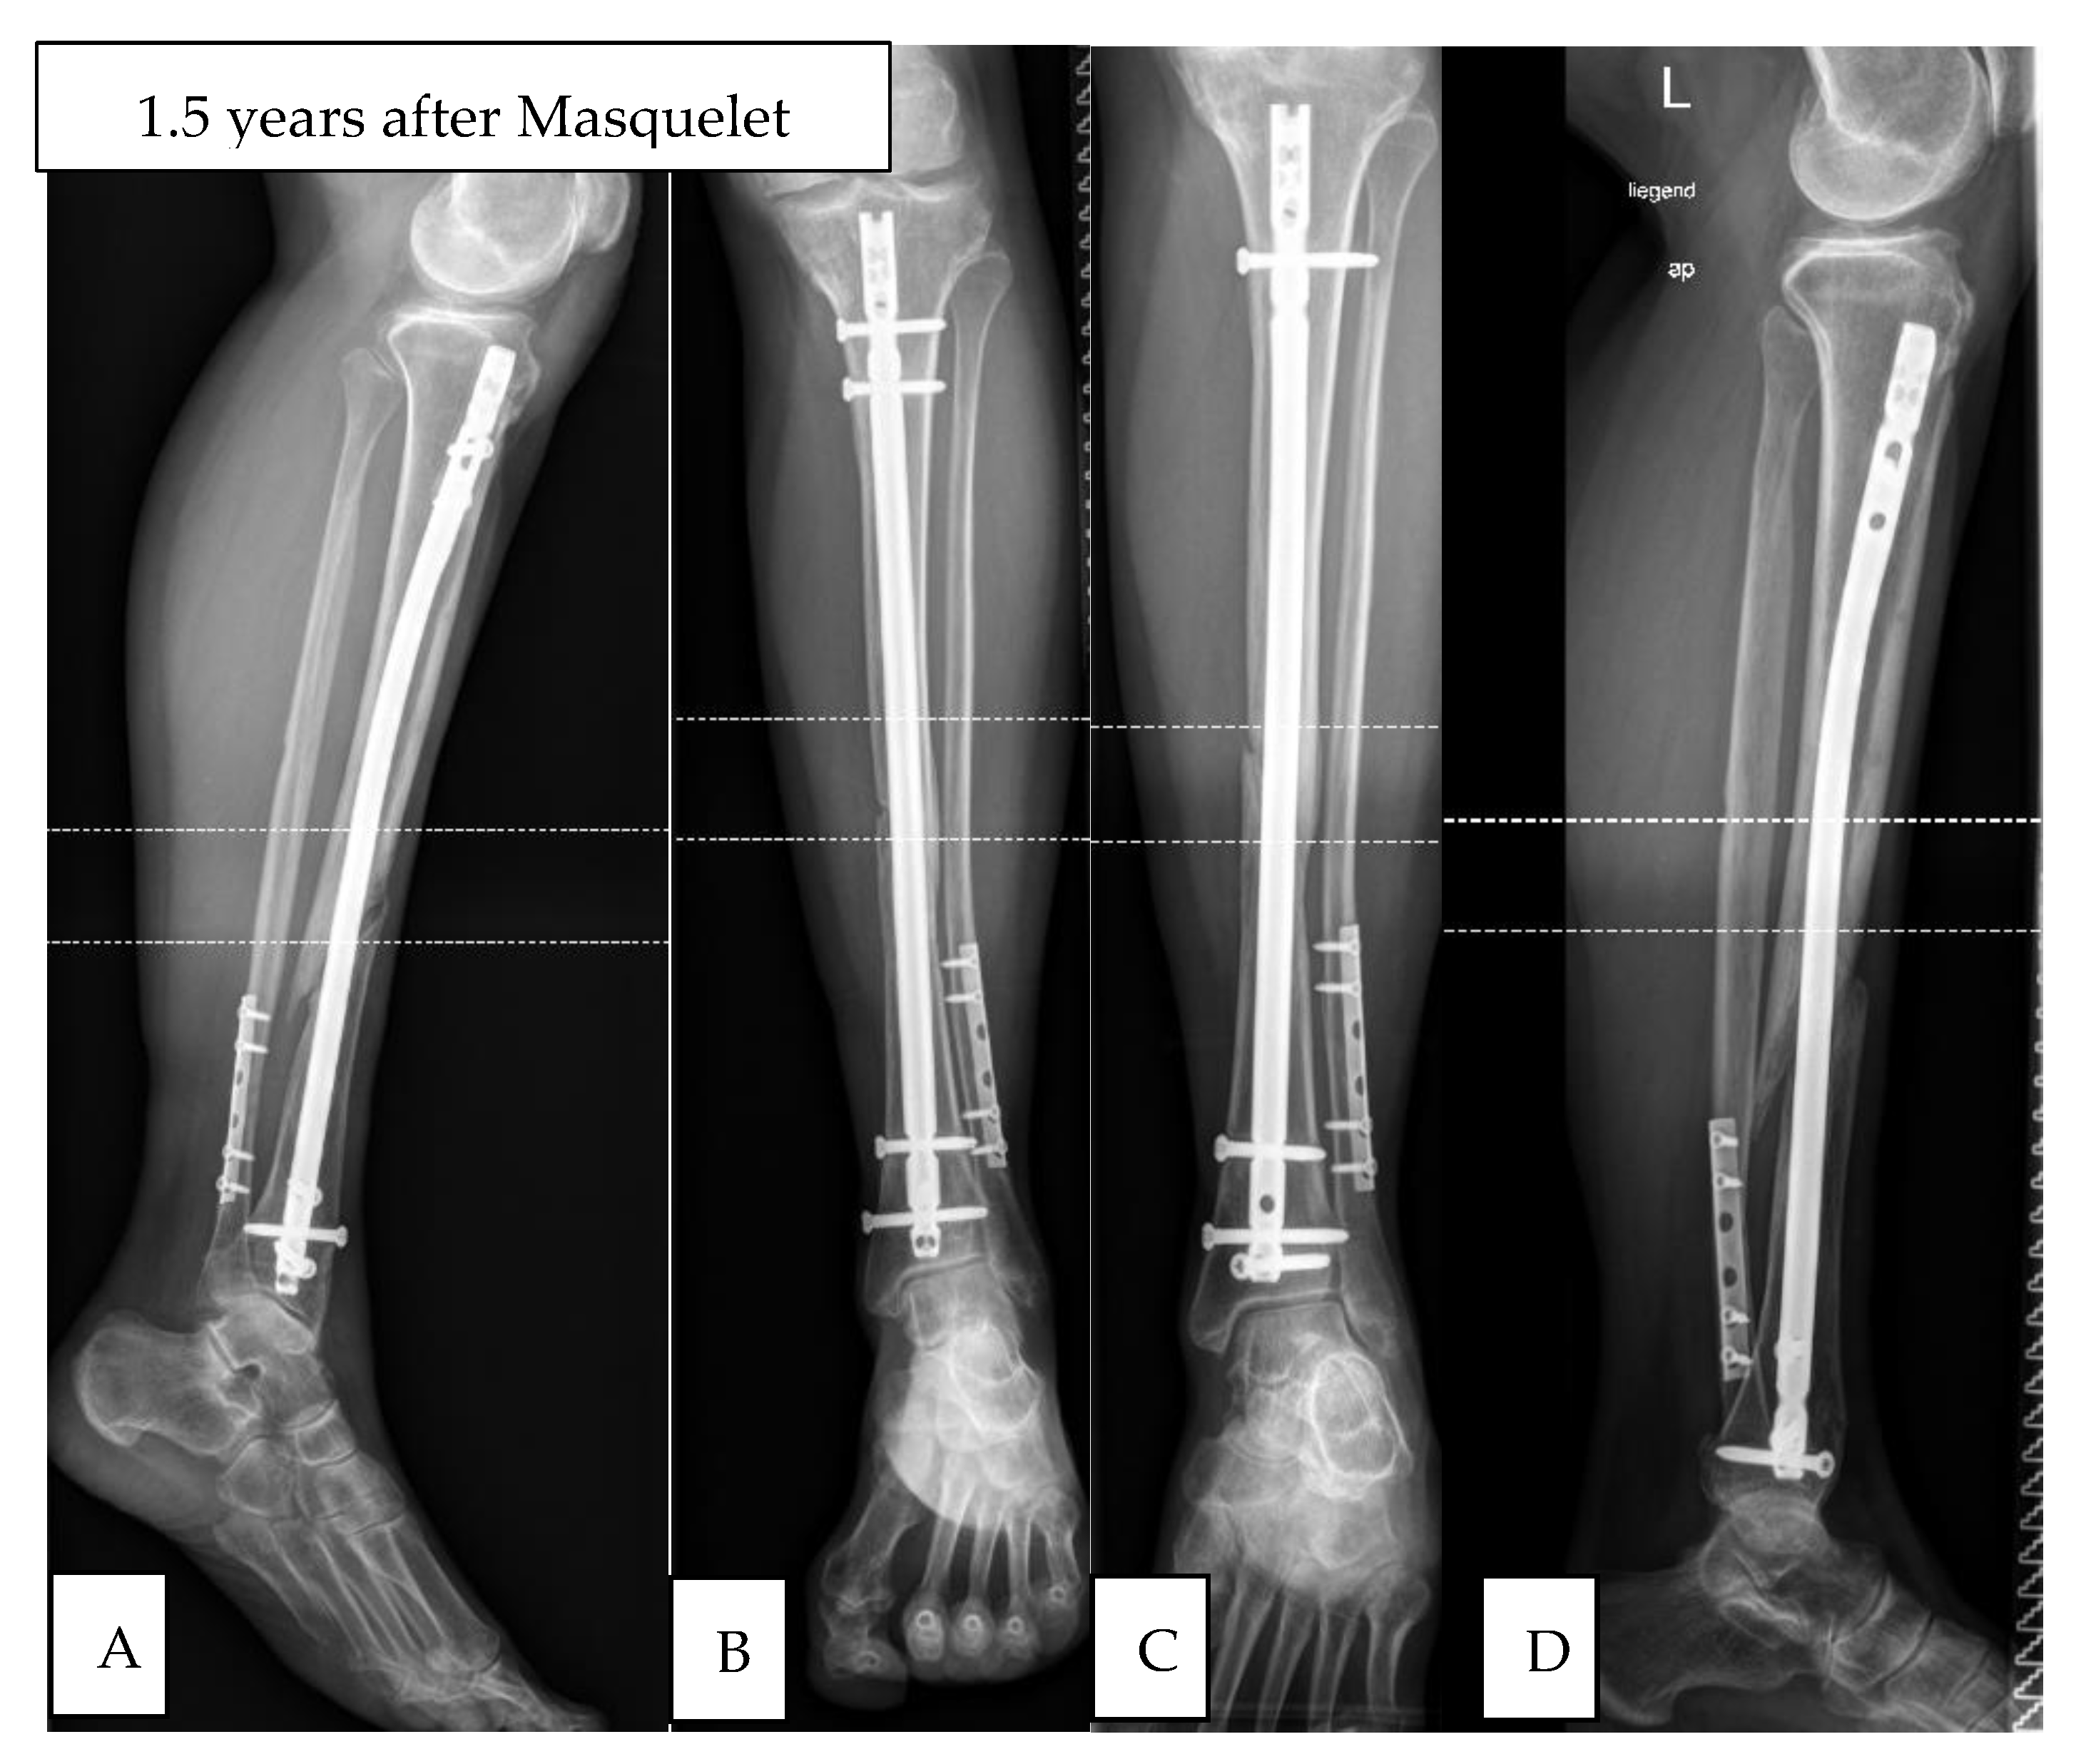

3.1. Study Group 1: Responders

3.2. Study Group 2: Non-Responder